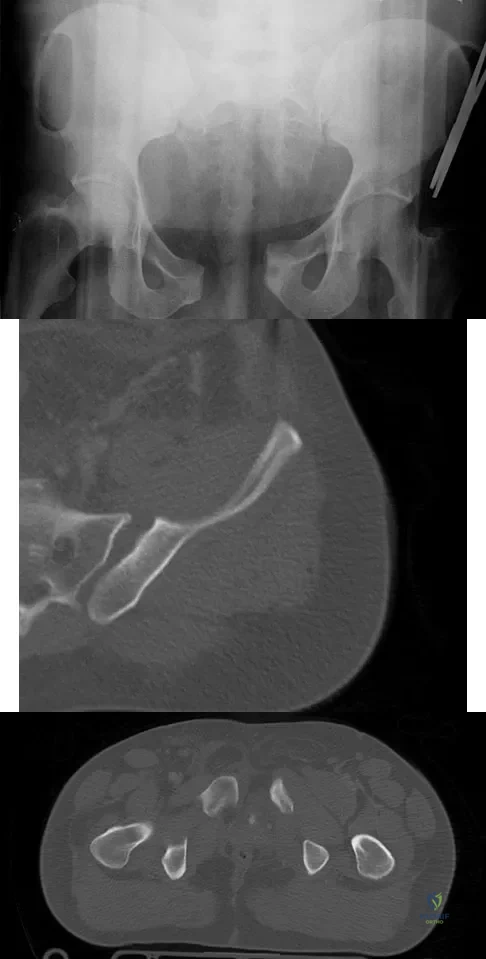

A 22-year-old cheerleader who fell from the top of a pyramid now reports anterior and posterior pelvic pain. A radiograph and CT scans are shown in Figures 43a through 43c. What is the best treatment for this injury?

Explanation